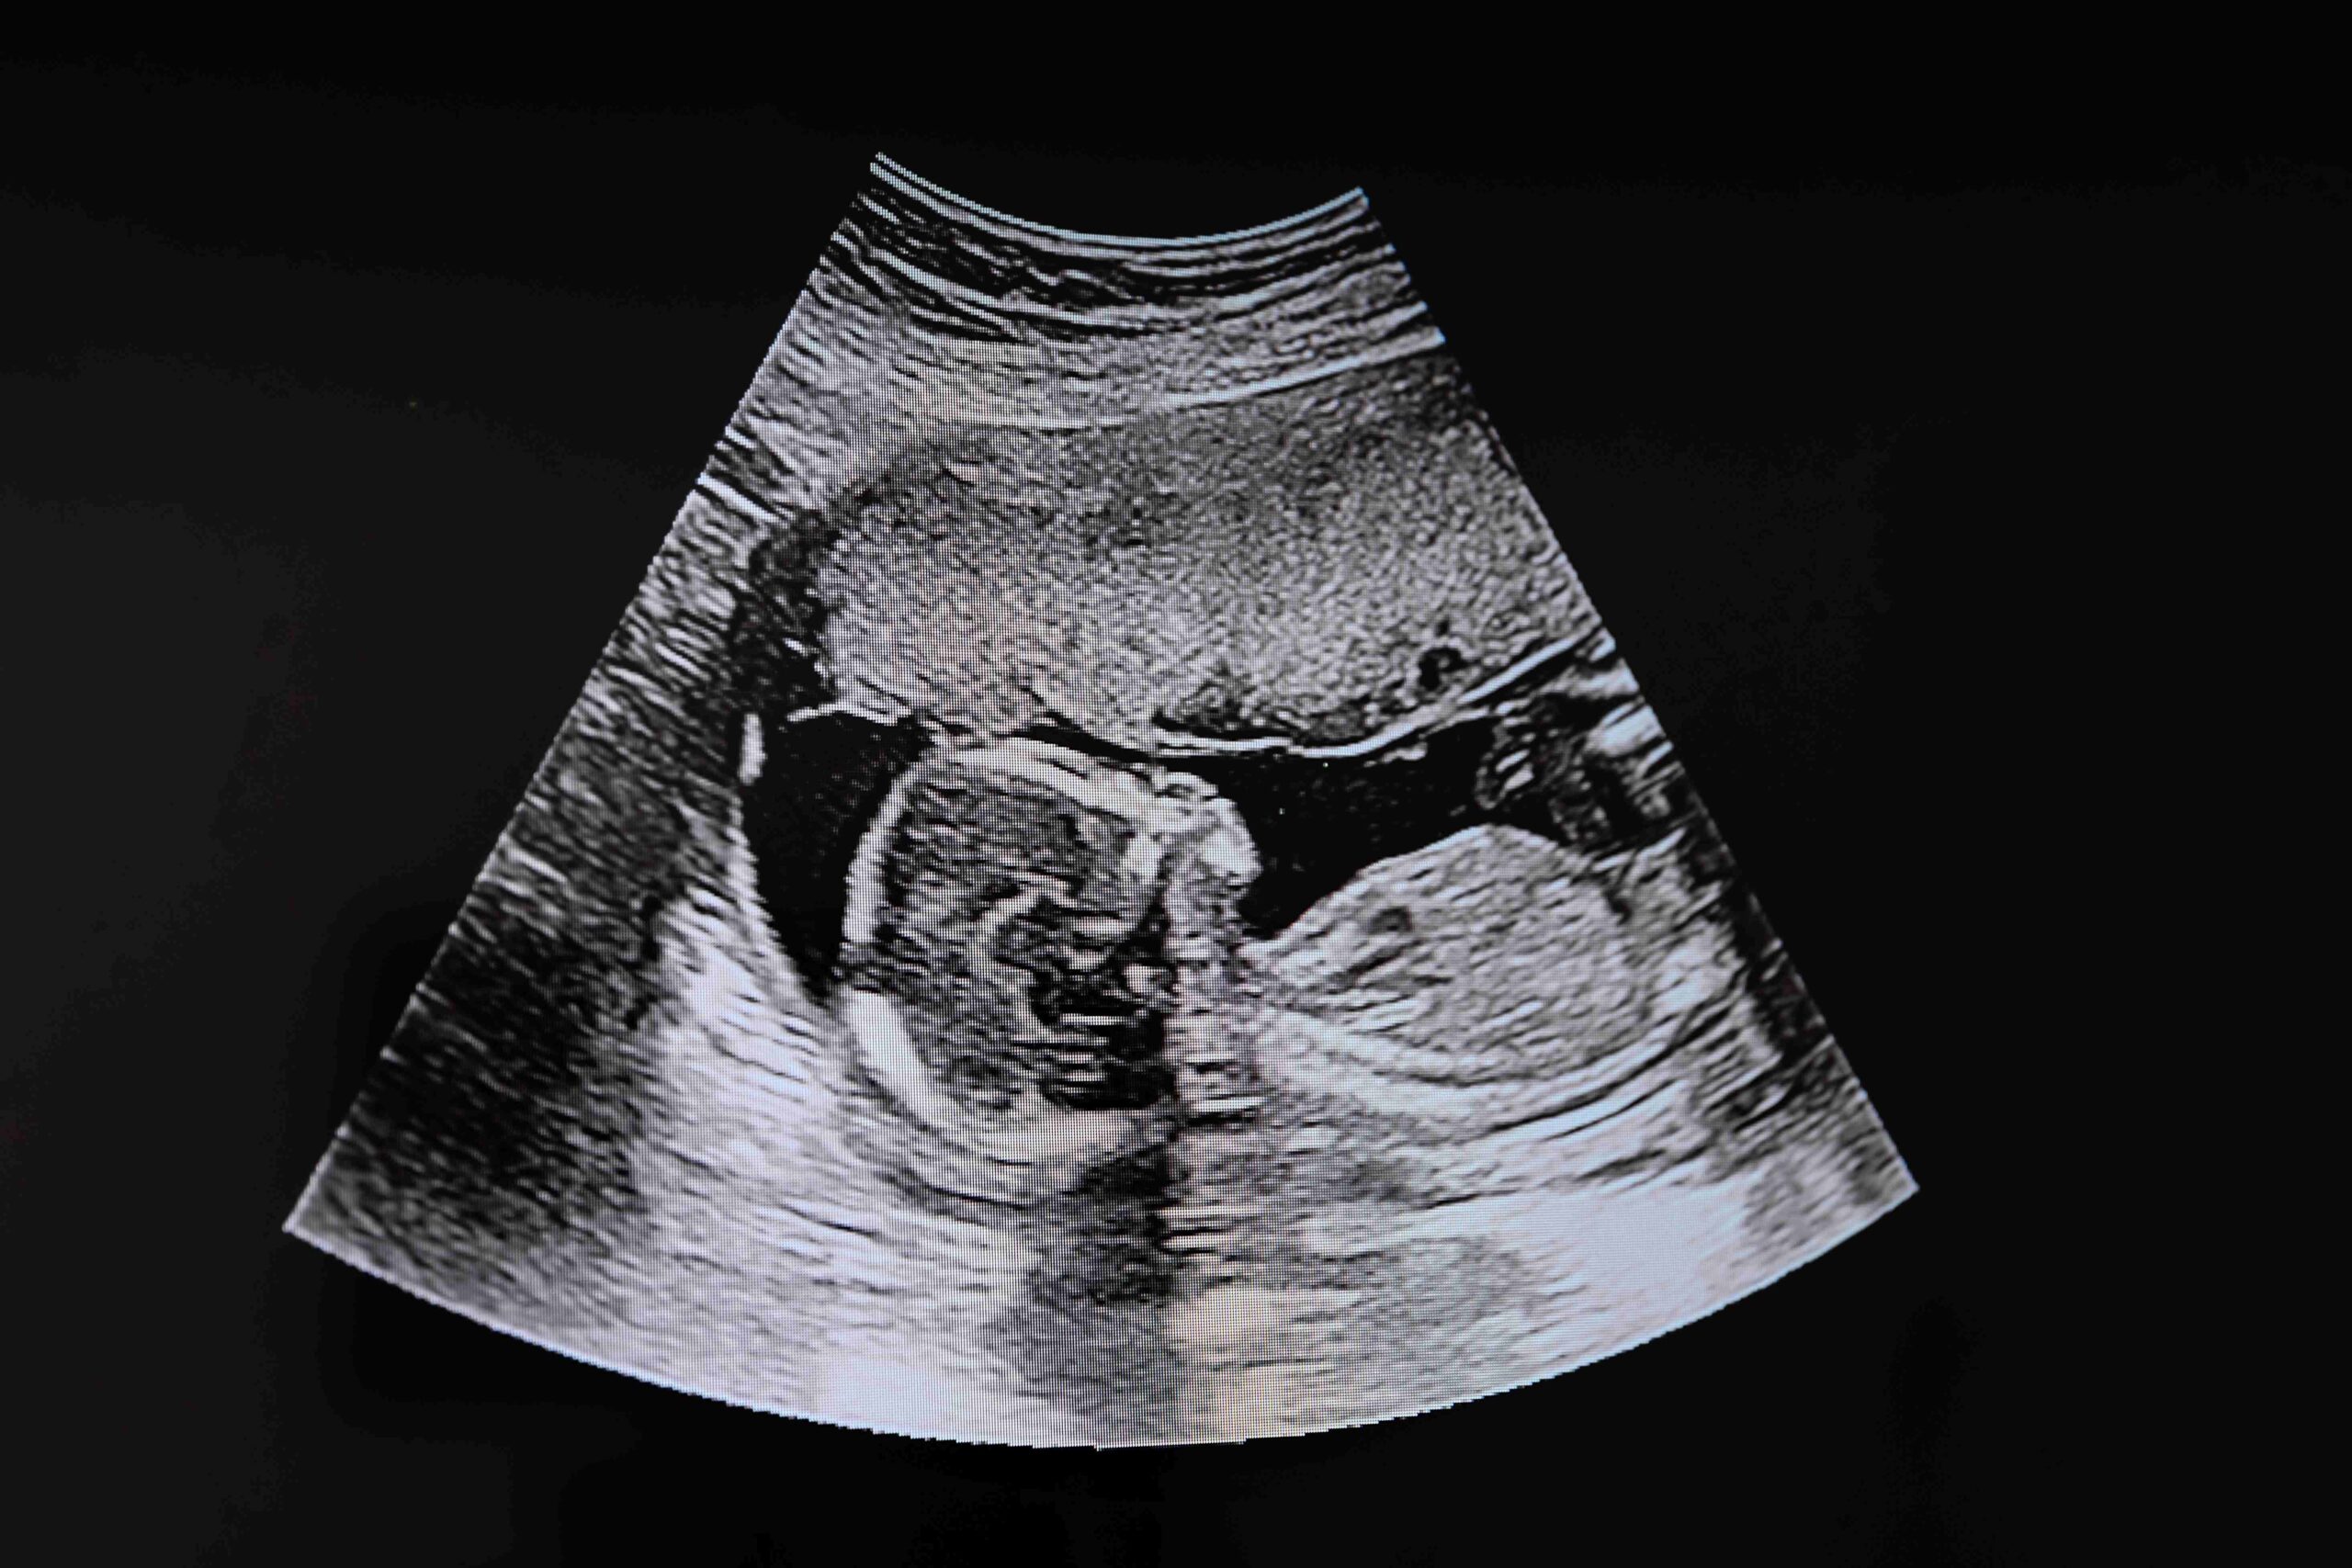

Coraz więcej kobiet korzysta z prywatnych badań ultrasonograficznych, licząc na szybszy dostęp do usług i komfortowe warunki. Tymczasem, jak ujawnia The Guardian, w wielu miastach Wielkiej Brytanii rośnie liczba klinik działających bez wykwalifikowanego personelu i przeprowadzających USG w ciąży.

Specjaliści NHS coraz częściej alarmują o przypadkach, w których prywatne kliniki popełniały błędy w diagnozach prenatalnych. Zdarzały się sytuacje, w których kobiety błędnie informowano o poronieniu lub wadach płodu. Jedna z pacjentek otrzymała wiadomość o utracie ciąży, a w szpitalu potwierdzono obecność zdrowego, żywego zarodka. W innych przypadkach nie wykryto ciąż pozamacicznych.

Eksperci z SoR zwracają uwagę również na przypadki, w których w prywatnych gabinetach skupiano się na ustaleniu płci dziecka, pomijając szczegółową ocenę rozwoju płodu. Gdy kobiety trafiały na badania w NHS, odkrywano m.in. wodogłowie, rozszczep kręgosłupa czy torbielowate nerki. Te problemy nie mogły rozwinąć się w kilka dni, co pokazuje, że wcześniejsze badania wykonano nieprofesjonalnie.